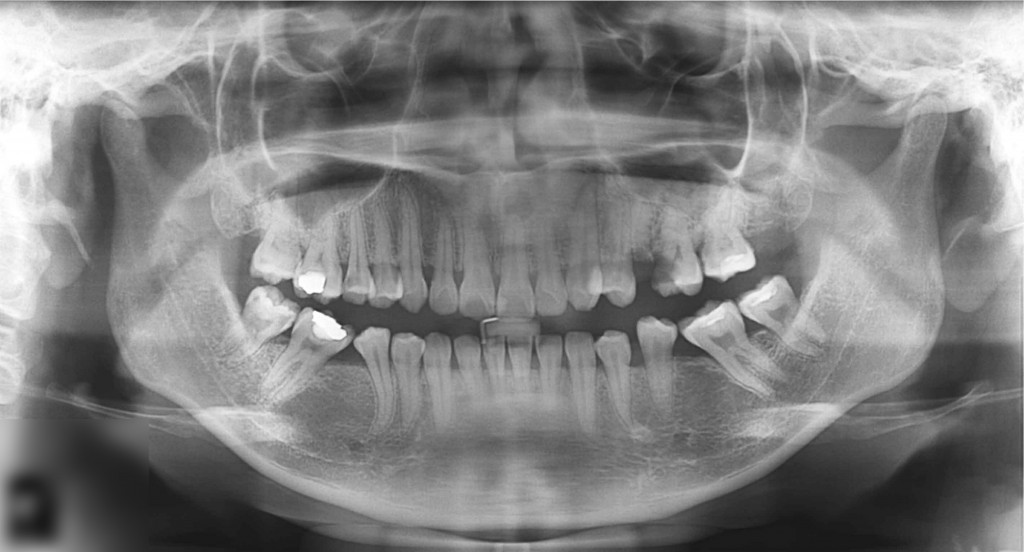

O nouă radiografie ne arată ameliorarea problemei inițiale. Tratamentele de canal au adus un aport substanțial la aceasta.